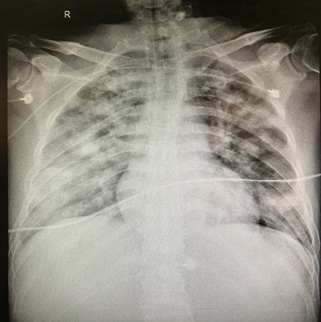

Figure 3 The Chest radiograph on November 8, 2020.

After admission in Jinyang Hospital, chest radiograph was performed, results showed that the manifestations of bilateral lung inflammation: The fuzzy bilateral lung markings, multiple patchy and patchy hyperdense shadows.